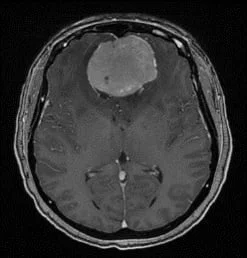

Un méningiome peut être diagnostiqué au scanner où il apparaît comme une masse ronde à la périphérie du cerveau, avec un épaississement de l’os au niveau de sa base d’insertion sur la méninge.

Il est plus fréquemment retrouvé sur une IRM sous forme d’une masse “blanche” après injection du produit de contraste intraveineux et entourée d’un œdème. Les méningiomes peuvent se rencontrer dans différentes localisations intra-crâniennes, plus ou moins facilement accessibles et qui conditionneront la technicité et les risques du geste qui vous sera proposé par votre chirurgien.